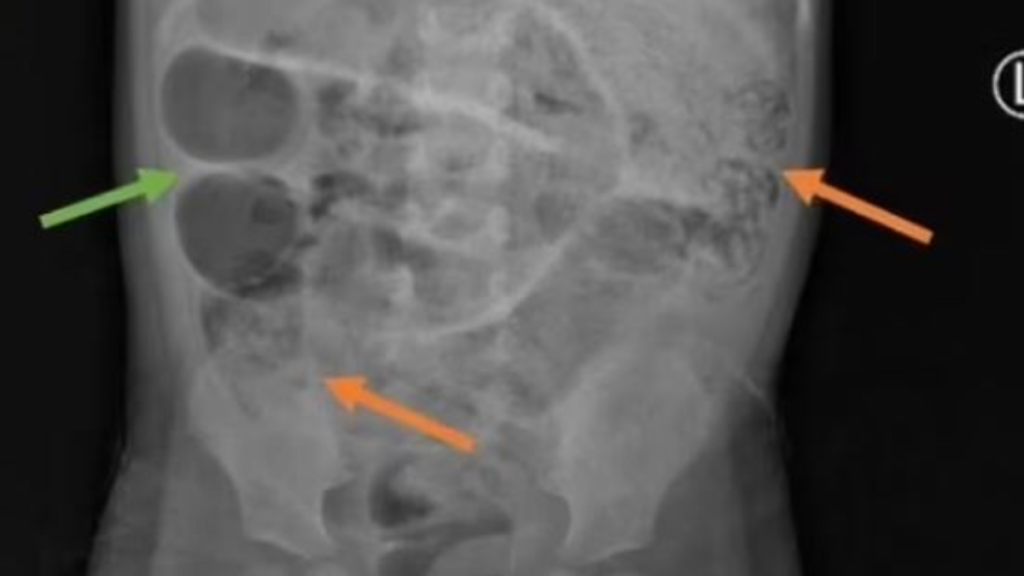

Endonezya’da üç yaşında bir çocuk, aylardır süren mide ağrısı, kabızlık ve ateş şikayetleriyle boğuşuyordu. Bir süre sonra kurt kusmaya başlayan çocuğun karnı da şişince hastaneye kaldırıldı. Çekilen röntgen filminde, ince bağırsağın üç farklı bölgesini tıkayan gri kitleler tespit edildi. Bu kitlelerin, tıbbi adıyla Ascaris lumbricoides olarak bilinen ve 35 cm uzunluğa ulaşabilen yuvarlak solucanlar olduğu anlaşıldı. Doktorlar, çocuğun kirli su içmiş veya çıplak ayakla dolaşırken bu solucanlara maruz kalmış olabileceğini düşünüyor. Tedavi edilmeyen vakalarda, bu solucanlar bağırsak delinmesine ve ölüme yol açabileceği için tehlikeli bir durum oluşturuyor. Uzmanlar hijyen kurallarına dikkat edilmesinin önemini vurguluyor. Yapılan tetkiklerde, çocuğun solucanların bağırsakta kana beslenmesi sonucu oluşan kronik kan kaybı nedeniyle kansız kaldığı da ortaya çıktı. Bu durum, vücudun kırmızı kan hücresi üretimini olumsuz etkileyerek demir eksikliğine yol açıyor.